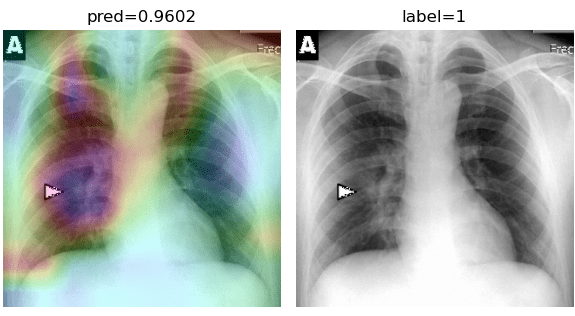

5.3 COVID-CXNet

To overcome the aforementioned issues and force the model’s attention to the correct regions of interest (ROIs), we introduce the COVID-CXNet. Our model is initialized with the pretrained weights from CheXNet. A dataset of 3,628 images, 3,200 normal CXRs and 428 COVID-19 CXRs, are divided into 80% as training-set and 20% as test-set. Batch size is set to 16, rather than 32 in previous models, regarding memory constraints. Grad-CAMs of the COVID-CXNet for random images are plotted in Fig. 15.

Refer to caption

Figure 15: Grad-CAM visualization of the proposed model over sample cases

More Grad-CAMs are available in Appendix A. Heatmaps are more accurate than previous models, while an accuracy of 99.04% and an f-score of 0.96 are achieved. Table 3 is the confusion matrix of the proposed model.